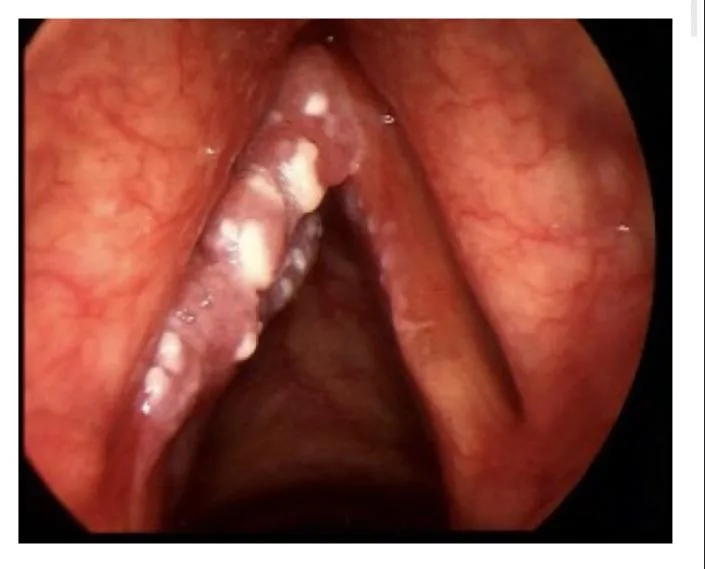

Vocal Nodules

A 34-year-old female teacher presented with a 1-year history of dysphonia and voice fatigue.

- A- Whatโs most likely the diagnosis?

- Vocal fold lesions secondary to vocal abuse and trauma

- B- What is the management?

- Voice therapy (voice rest), if no response surgical removal

- A- What is the diagnosis?

- Vocal Cord nodules

- Speech therapy

left Vocal Cord Nodule,

bilateral? CC